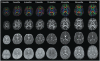

The human brain rapidly develops during the final weeks of gestation and in the first two years following birth. Diffusion tensor imaging (DTI) is a unique in vivo imaging technique that allows three-dimensional visualization of the white matter anatomy in the brain. It has been considered to be a valuable tool for studying brain development in early life. In this review, we first introduce the DTI technique. We then review DTI findings on white matter development at the fetal stage and in infancy as well as DTI applications for understanding neurocognitive development and brain abnormalities in preterm infants. Finally, we discuss limitations of DTI and potential valuable imaging techniques for studying white matter myelination.